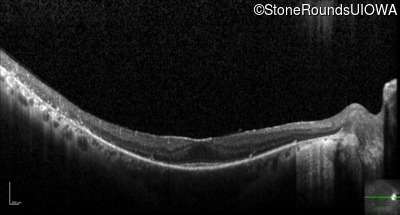

Optical Coherence Tomography - Right - 20/20

Exemplar / OCT Stack

OCT Stack